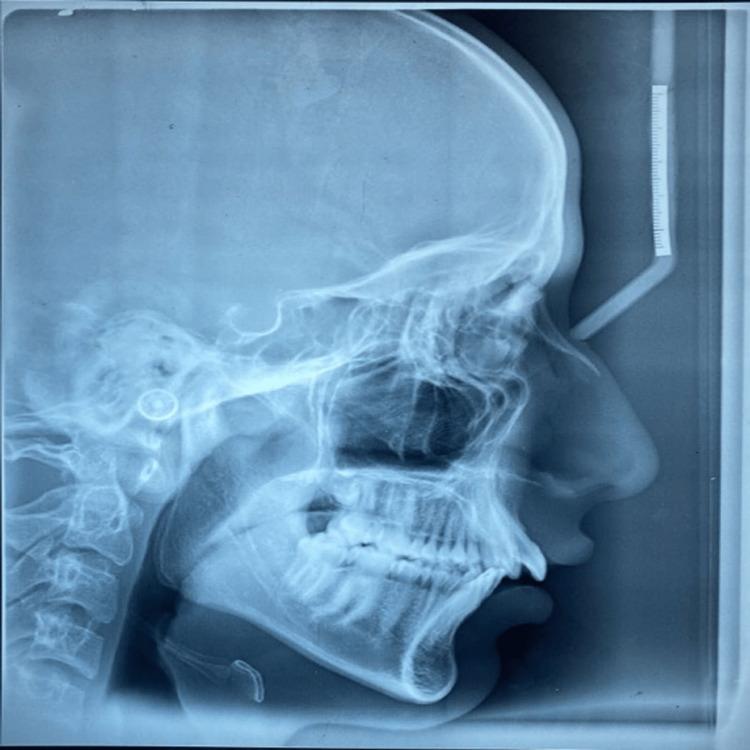

Background and objectives The nose is one of the major focuses of face attractiveness. Through careful evaluation of the soft tissue drape, a treatment plan can be designed to enhance a patient's facial attractiveness. The aim of this study was to evaluate and assess the variations in nasal morphology among class I malocclusion and class II horizontal and class II vertical malocclusion. Material and method Lateral cephalograms of 27 patients were taken and consisted of three groups: skeletal class I malocclusion, class II horizontal malocclusion, and class II vertical malocclusion. The various linear and angular measurements specific to nose were assessed. Results and conclusion In class II and class I malocclusion, the nose is observed to be straight and convex, respectively. Additionally, compared to class II horizontal malocclusion, it is more convex in class II vertical malocclusion. Vertical growers or high-angle cases are more likely to have a nose with an increased inclination toward nasal dorsum convexity than horizontal growers or low-angle instances.

背景与目的 鼻子是面部吸引力的主要关注点之一。通过对面部软组织覆盖情况的仔细评估,可以设计出治疗方案来提升患者的面部吸引力。本研究的目的是评估和分析安氏I类错牙合、安氏II类水平型错牙合和安氏II类垂直型错牙合患者的鼻形态差异。材料与方法 对27例患者拍摄头颅侧位片,分为三组:骨骼I类错牙合、II类水平型错牙合和II类垂直型错牙合。评估了鼻子特定的各种线性和角度测量值。结果与结论 在II类和I类错牙合中,鼻子分别表现为直和凸。此外,与II类水平型错牙合相比,II类垂直型错牙合中的鼻子更凸。垂直生长型或高角病例比水平生长型或低角病例更有可能出现鼻背凸度倾斜增加的鼻子。